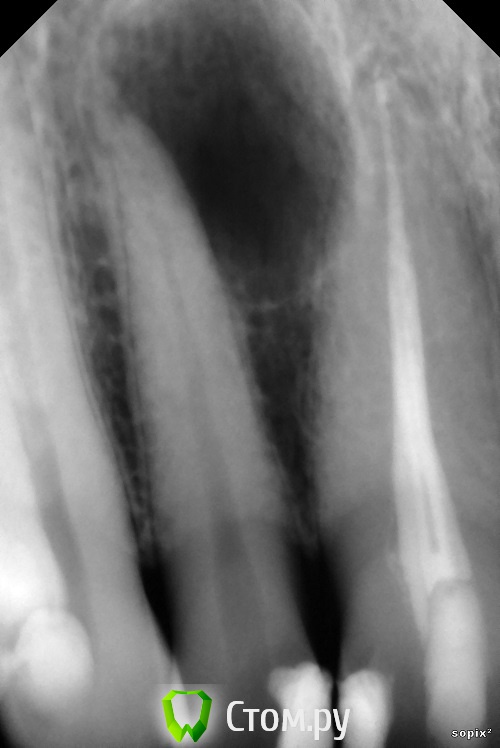

Dr.Sham Опубликовано 9 ноября, 2014 Поделиться Опубликовано 9 ноября, 2014 (изменено) Пришла пациентка за винирами, сделали снимки, увидили красоту Виниры на время отложили.Начал лечить, получил обострение, отмылся повторно, симптомы ушли.2 раза кальций поменял, т.к. после первого раза еще канал влажный был.Запаковал или волной, или сквирт был, уже не вспомнить.Вот результаты, критикуйте 05.1209.1311.14 Изменено 9 ноября, 2014 пользователем Dr.Sham 11 Ссылка на комментарий

M@estro Опубликовано 9 ноября, 2014 Поделиться Опубликовано 9 ноября, 2014 Перепреп детектед а так норм Ссылка на комментарий

Shaid Опубликовано 10 ноября, 2014 Поделиться Опубликовано 10 ноября, 2014 Перепреп детектед Имеется ввиду овер в 1.2 или чрезмерное расширение устьевой и средней части в 1.1? Ссылка на комментарий